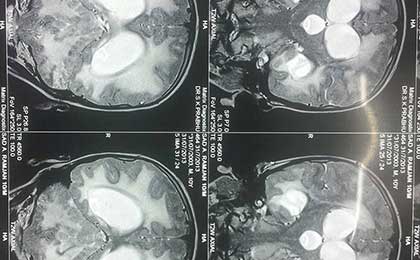

Obstructive Hydrocephalus 2 Pre Op Mri